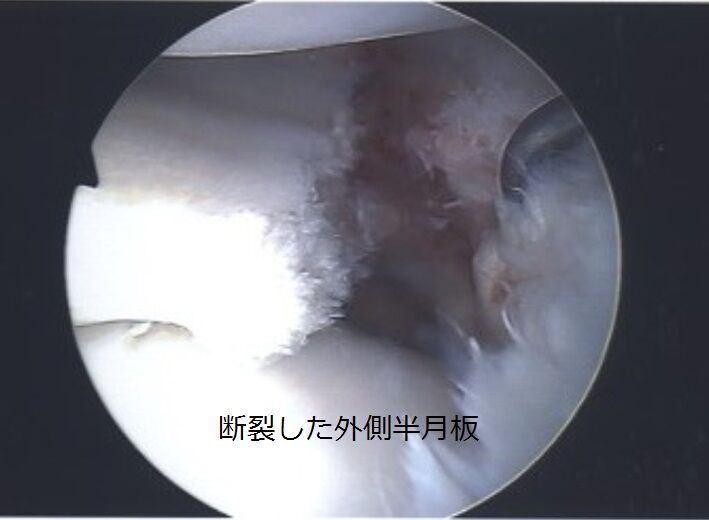

| J3最下位の岩手、4月に負傷していたMF弓削翼が手術…右ヒザ外側半月板損傷で全治6カ月で今季絶望「申し訳ない気持ちで一杯」 …表した。 弓削は4月4日のトレーニング中に負傷。検査の結果、右ヒザ外側半月板損傷と診断され、6月24日に手術を実施したという。 なお、全治に関しては手… (出典:超WORLDサッカー!) |